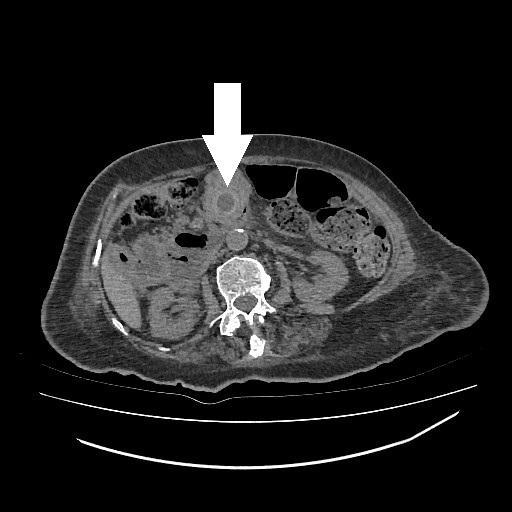

A. Miros, A. Paśnikowska, M. Romanowska, Zespół Barnarda jako rzadka przyczyna niedrożności jelita cienkiego... 53

ści o opisywanej etiologii, zwłaszcza gdy chorym jest osoba w wieku podeszłym. Postawienie szybkiego rozpoznania bywa utrudnione ze względu na często współwystępujący z wiekiem zespół otępienny, który uniemożliwia zebranie wywiadu. Istotną rolę w diagnostyce odgrywają badania RTG oraz TK. Istnieje wiele możliwości terapeutycznych, jednak zawsze należy spośród nich wybrać tę najbardziej optymalną i bezpieczną dla pacjenta, nie siląc się na jednoczasowe, duże operacje odtwórcze. W sytuacjach takich jak opisana ryzyko powikłań związanych z wykonaniem obciążającej i rozległej operacji może przeważać nad przewidywaną korzyścią z zabiegu.

Piśmiennictwo

1. Halabi W.J., Kang C.Y., Ketana N. et al.: Surgery for gallstone ileus: a nationwide comparison of trends and outcomes. Ann Surg 2014; 259(2): 329-335.

2. Tsang C.F.: A rare case of gallstone ileus – the unanswered question. J Surg Case Rep 2021; 2021(4): rjab164.

3. Lourenço S., Pereira A.M., Reis J. et al.: Gallstone ileus: an improbable cause of mechanical small bowel obstruction. Cureus 2020; 12(11): e11460.